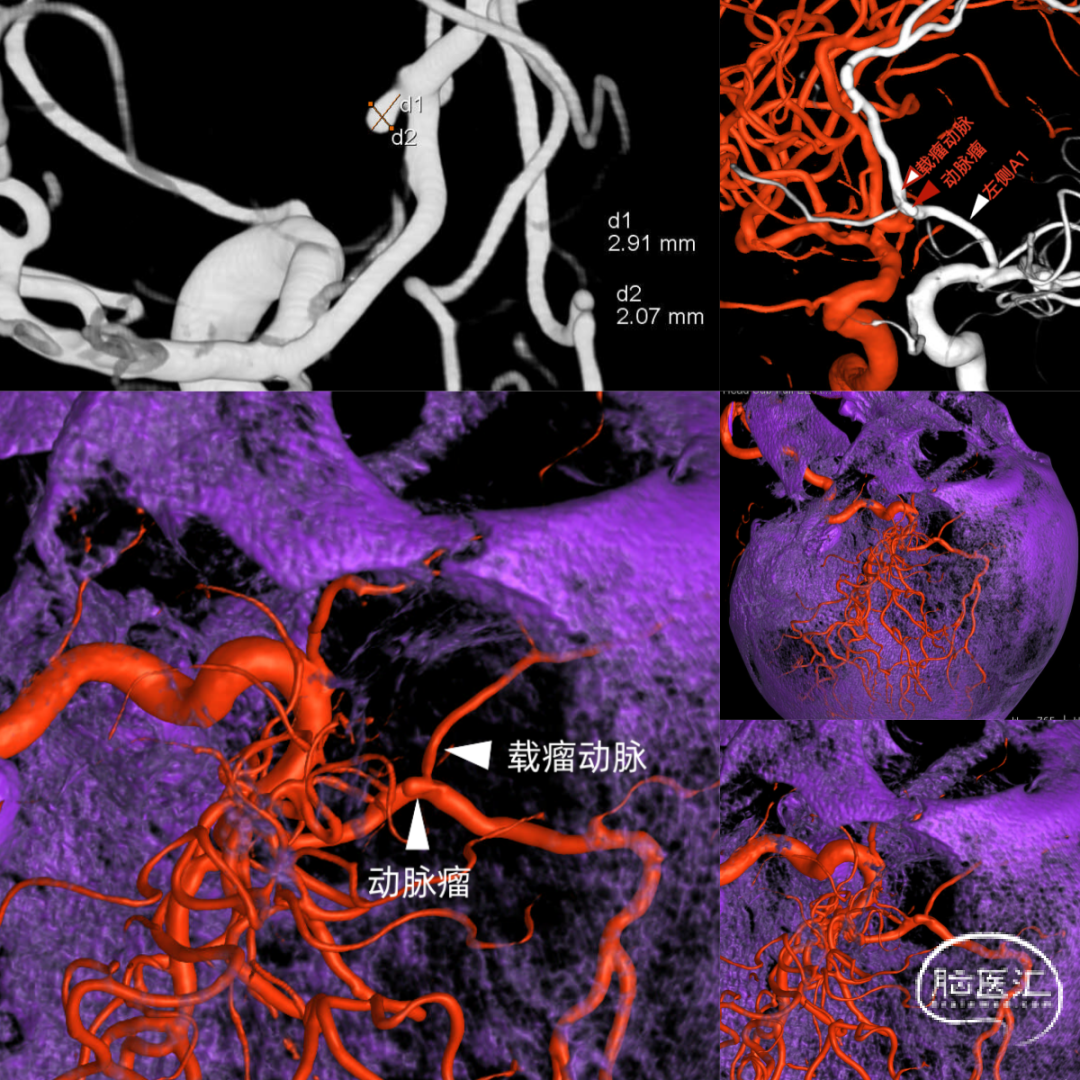

2、在进行术前准备拟行脑血管造影时,患者突发癫痫大发作,予以抗癫痫处理后,全麻气管插管下行DSA造影,提示左侧大脑前动脉分支-额极动脉动脉瘤(图2)。

图2 DSA额极动脉动脉瘤

该例患者术前CTA未见明显动脉瘤,但出血部位高度疑诊动脉瘤,位于前交通或A2段动脉瘤可能。DSA造影明确为额极动脉动脉瘤。术中暴露至前交通复合体时因A2明显增粗,易误判为动脉瘤,索性术前充分阅片,判断为A2。切除部分直回后先暴露动脉瘤,试夹闭动脉瘤后,分离周围空间,可见载瘤动脉误夹,予以反复调整后完整夹闭瘤颈,并保持载瘤动脉通畅。ICG荧光造影证实动脉瘤夹闭完全,载瘤动脉通畅。后续康复满意。